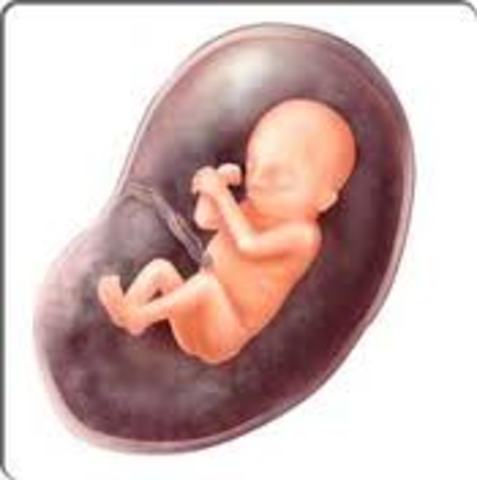

Period of the Fetus

Inside witha baby The time period from the end of two months to birth

Month Four the baby is beginning to gain control of their muscle movements. they can even make facial expressions in response to changes in the uterine environment. \the uterus and skin need twice as much blood as usual, and the kidneys need 25% more blood than usual. the uterus has outgrown the mothers pelvis and will be forced into the abdomen, which will decrease her lung capacity.